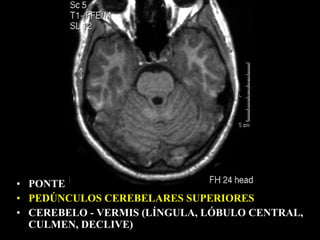

• PONTE

• PEDÚNCULO CEREBELARES MÉDIOS / CORPOS

MEDULARES        NÓDULO

VERMIS   ÚVULA

PIRÂMIDE

• CEREBELO                 FLÓCULO

HEMISFÉRIOS

SEMILUNAR

• ARTÉRIA BASILAR

• IV VENT.

• CISTERNAS PRÉ-PONTINA

CEREBELO-PONTINA

• CONDUTOS AUDITIVOS

INTERNOS

• PONTE - COLÍCULOS FACIAIS

• PEDÚNCULOS CEREBELARES MÉDIOS / CORPOS MEDULARES

• CEREBELO

VÉRMIS - NÓDULO, ÚVULA, PIRÂMIDE

• CISTERNA      HEMISFÉRIOS

PRÉ-PONTINA

• C.A.I.       CEREBELO-PONTINA

• PEDÚNCULOS CEREBELARES SUPERIORES

• CEREBELO - VERMIS (LÍNGULA, LÓBULO CENTRAL,

CULMEN, DECLIVE)